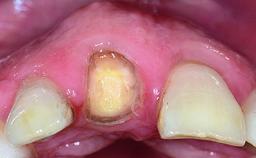

Replacement of an Ankylosed Upper Left Central Incisor: Bone Augmentation and Socket Grafting, Late Placement of an RC Bone Level Implant

A 15-year-old male patient was referred to us by his pediatric dentist in June 2004 for evaluation of treatment options for his failing tooth 21. The patient had recently seen an endodontist for internal bleaching and been advised that there had been significant resorption and ankylosis. The patient’s mother was concerned because the tooth appeared shorter than the adjacent one. His past dental history was significant for trauma (September 2001), where the tooth had been avulsed and reimplanted. Teeth 11 and 21 had been endodontically treated.